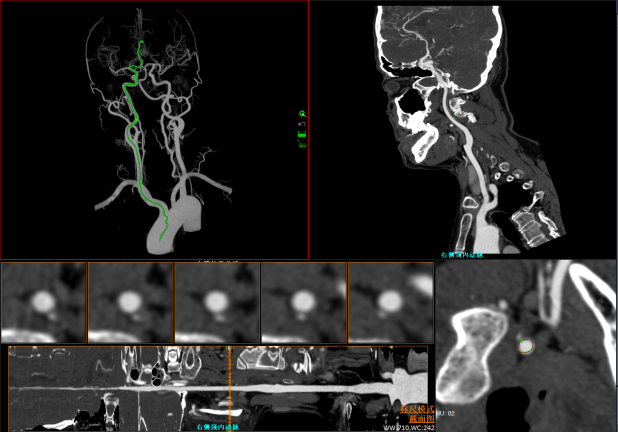

Nghiêng kỹ thuật số ±50° giúp quy trình nhanh hơn.

Chỉ với 1 click tự động xác định chính xác phạm vi quét theo giao thức đã chọn, giảm thiểu điều chỉnh thủ công phức tạp

Chỉ với 1 click định vị chính xác iso-center, tối ưu hình ảnh và liều tia, giảm thiểu phơi nhiễm